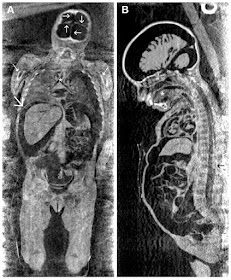

Este extraordinario (en su amplio sentido) estado de conservación del cuerpo de Rosalía, activó la alarma de los más escépticos -casi conspiranoicos-. Era tan bella y perfecta, que llegaron a afirmar que el cuerpo de Rosalía había sido sustituido por una réplica idéntica de cera (como se ha sugerido también con Mao Zedong) y que todo era un reclamo turístico, dado que desde el principio estaba expuesto públicamente en las Catacumbas de los Capuchinos de Palermo y era la estrella del lugar. Como consecuencia, en julio de 2008, el equipo formado por Stephanie Panzer, Albert R. Zink, y Dario Piombino-Mascali le practicó radiografías anteroposteriores. No sin cierta dificultad. Salafia había pensado en todo y el féretro estaba tapado por una doble plancha de cristal sellada con cera para evitar la entrada de humedad, y absolutamente recubierto de plomo, lo que imposibilitaba la visualización del interior del cuerpo de Rosalía. La última opción era darle más potencia a la radiación para tratar de ver algo, a costa de la calidad, pero menos da una piedra.

¡Y lo vieron! Observando in situ las imágenes que mostraba la pantalla, no daban crédito a lo que veían. No solo el cuerpo era auténtico (de muñeca de cera, nada) sino que el cerebro estaba en perfecto estado (un poco más pequeño, claro. Había encogido un poquito), así como el resto del cuerpo. Además, se diferenciaban perfectamente varios órganos en las radiografías. Bueno... todo lo perfectamente que permitía el blindaje de plomo.

![]() |

| Radiografía anteroposterior de cabeza, pecho y abdomen, que muestra los hemisferios cerebrales moderadamente encogidos, parte del pulmón derecho y del hígado y el riñón izquierdo. La mala calidad de la imagen se debe a la superposición del ataúd forrado de plomo. Fuente |

En diciembre de 2010, Panzer y su equipo, de nuevo tuvieron la oportunidad de analizar el cuerpo de la pequeña Rosalía con la novedosa técnica llamada multidetector computed tomography (MDCT) de cuerpo entero, el súmmun de las técnicas de imagen de estudio de momias. La MDCT viene a ser una tomografía axial computerizada o TAC (o escáner) para entendernos. Por supuesto, debían usar un método no invasivo que no perjudicara el estado del cuerpo. Esta tecnología permitió observar el esqueleto completo, los tejidos blandos y las cavidades internas.

| MDCT de cuerpo entero mostrando cabeza, tronco y muslos. Las flechas punteadas muestran hueso esponjoso. Las flechas cortas señalan la duramadre del cerebro y la flecha larga señala el diafragma que separa cavidad torácica de la abdominal. El * señala la tráquea y la lengua intacta. Fuente |

¿Y qué demostró el análisis con esta técnica? Pues que el estado de conservación de Rosalía es excelente (por fuera ya se nota), especialmente de los órganos internos. Se pudo confirmar la causa de la muerte por neumonía gracias al diagnóstico radiológico (recordad que el TAC es una técnica actual de diagnóstico clínico de alta definición) y a que por supuesto, los órganos estaban en un estado excepcional. Sin embargo, a pesar de tanta tecnología, es imposible saber qué cambios sufrirá el cuerpo en el futuro ni cuándo.